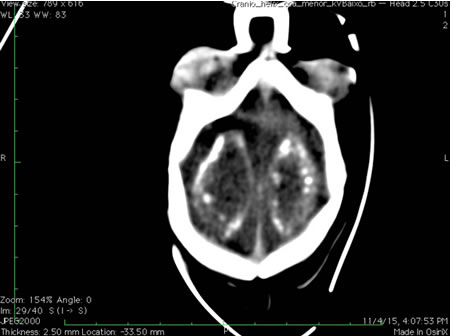

CT scan of the head of an infant with Zika virus infection showing a clear distribution of periventricular calcifications

From the personal collection of Dr Geraldo Furtado, MD, MSc (used with permission)